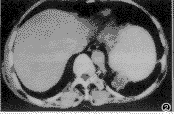

胸部CT检查: 平扫示左肺下叶后基底段主动脉旁一类圆形肿块,最大径约6.5cm,有包膜,其内低密度,均匀,CT值为15HU(图1)。增强扫描示包膜强化,但其内低密度处不强化,并见胸主动脉左后方有一分支伸向肿块(图2、3)。CT诊断为左肺下叶肺隔离症。

图1 CT平扫示左肺下叶后基底段脊柱旁胸主动脉后方一肿块,有包膜,其内为低密度,CT值为15HU